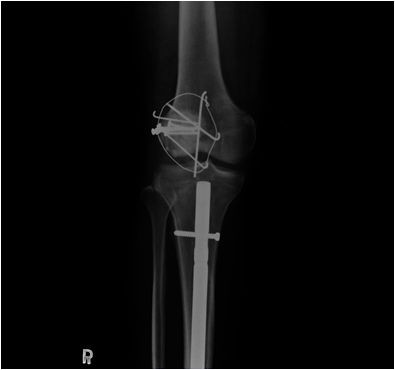

圖:手術治療前後的膝蓋與小腿。

圖:為了保住洪國程的右腿,鄺世通醫師用上鋼板、鋼索、補丁等各種可以的治療方式。

而當時的主治醫師就是個性直率低調,被同事與後進同仁暱稱為鄺爺的骨科鄺世通醫師,這個在鄺醫師口中的小骨折,其實是包含髖關節、大腿股骨、膝蓋髕骨、與小腿脛骨等多處粉碎性骨折的複雜個案,不論是X光檢查,還是電腦斷層檢查,都能看見因為強力撞擊穿出髖關節的股骨,還有粉碎的髕骨,歷經數個小時的開刀,才救回洪國程先生的性命與右腿。